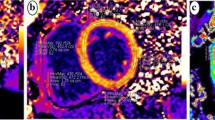

T1MyoPre, T1MyoPost, T1BloodPre, and T1BloodPost were the T1 measurements obtained from the myocardium and from the blood before and after the contrast enhancement, respectively (Fig. 1). The hematocrit level was obtained via routine hematological examination of the patients 1 to 7 days before CMR scanning.

T1 maps and GLS curve of typical cases in each group. A represents the Native T1 = 1037 ms, Post contrast T1 = 411 ms, ECV = 25%, and GLS = -22.5% of a control subject; B represents the Native T1 = 1062 ms, Post contrast T1 = 436 ms, ECV = 26%, and GLS = -15.8% of a hypertensive patient; C represents the Native T1 = 1051 ms, Post contrast T1 = 380 ms, ECV = 27%, and GLS = -14.5% of a normotension T2DM patient; D represents the Native T1 = 1097 ms, Post contrast T1 = 442 ms, ECV = 32%, and GLS = -10.7% of a hypertensive T2DM patient